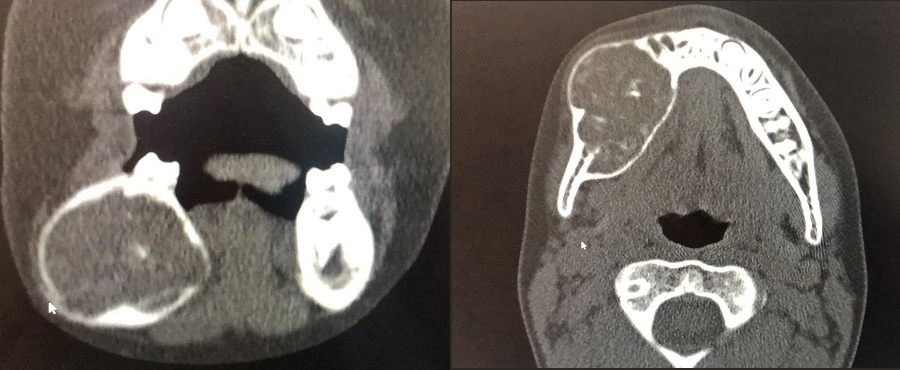

Paciente de 9 años que acude a consulta por bulto en zona mandibular de 2 meses de evolución, de consistencia dura, sin dolor ni inflamación asociada, ni infecciones previas. En ecografía clínica realizada en nuestro centro se objetiva lesión que produce protrusión de la cortical del hueso maxilar inferior, sin adherirse a tejidos blandos y con captación de Doppler de forma periférica. En la radiografía (Figura 1) solicitada posteriormente, se visualiza lesión lítica en rama derecha mandibular, expansiva, sin clara interrupción de la cortical que mide 3,6 cm, siendo sugestiva de benignidad. Con estos datos se deriva al paciente a Urgencias para valoración por Cirugía Maxilofacial, que amplía el estudio con analítica sanguínea, TAC (Figura 2) y ortopantomografía (Figura 3). Tras los resultados de las pruebas complementarias, entre los posibles diagnósticos diferenciales se encuentra el fibroma osificante de mandíbula. Se procede a su resección completa quirúrgica con buenos resultados y con biopsia que confirma el diagnóstico de fibroma osificante con focos sugestivos de quiste óseo aneurismático secundario. En el TAC de control se visualiza hueso inmaduro que ha ido ocupando la zona del defecto, sin evidenciarse recidiva.

Figura 2. TAC